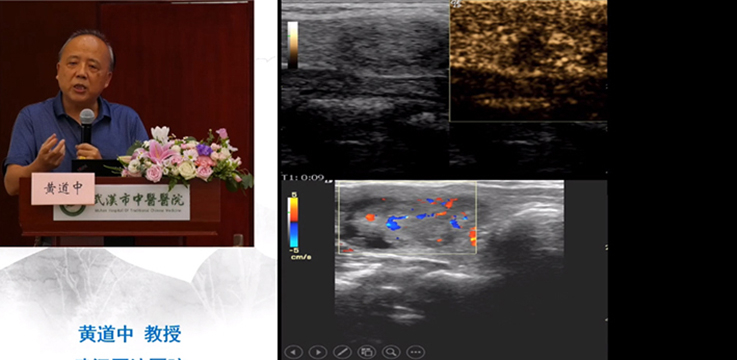

• 醫(yī)學直播 武漢市中醫(yī)醫(yī)院漢陽院區(qū) 超聲造影與介入的臨床應用

會上黃道中教授、楊順實教授、余曉梅教授、曾書娥教授、彭國平教授、閔潔醫(yī)師作了主旨演講,分享了他們的經(jīng)驗,并同各位學員進行了案例討論。